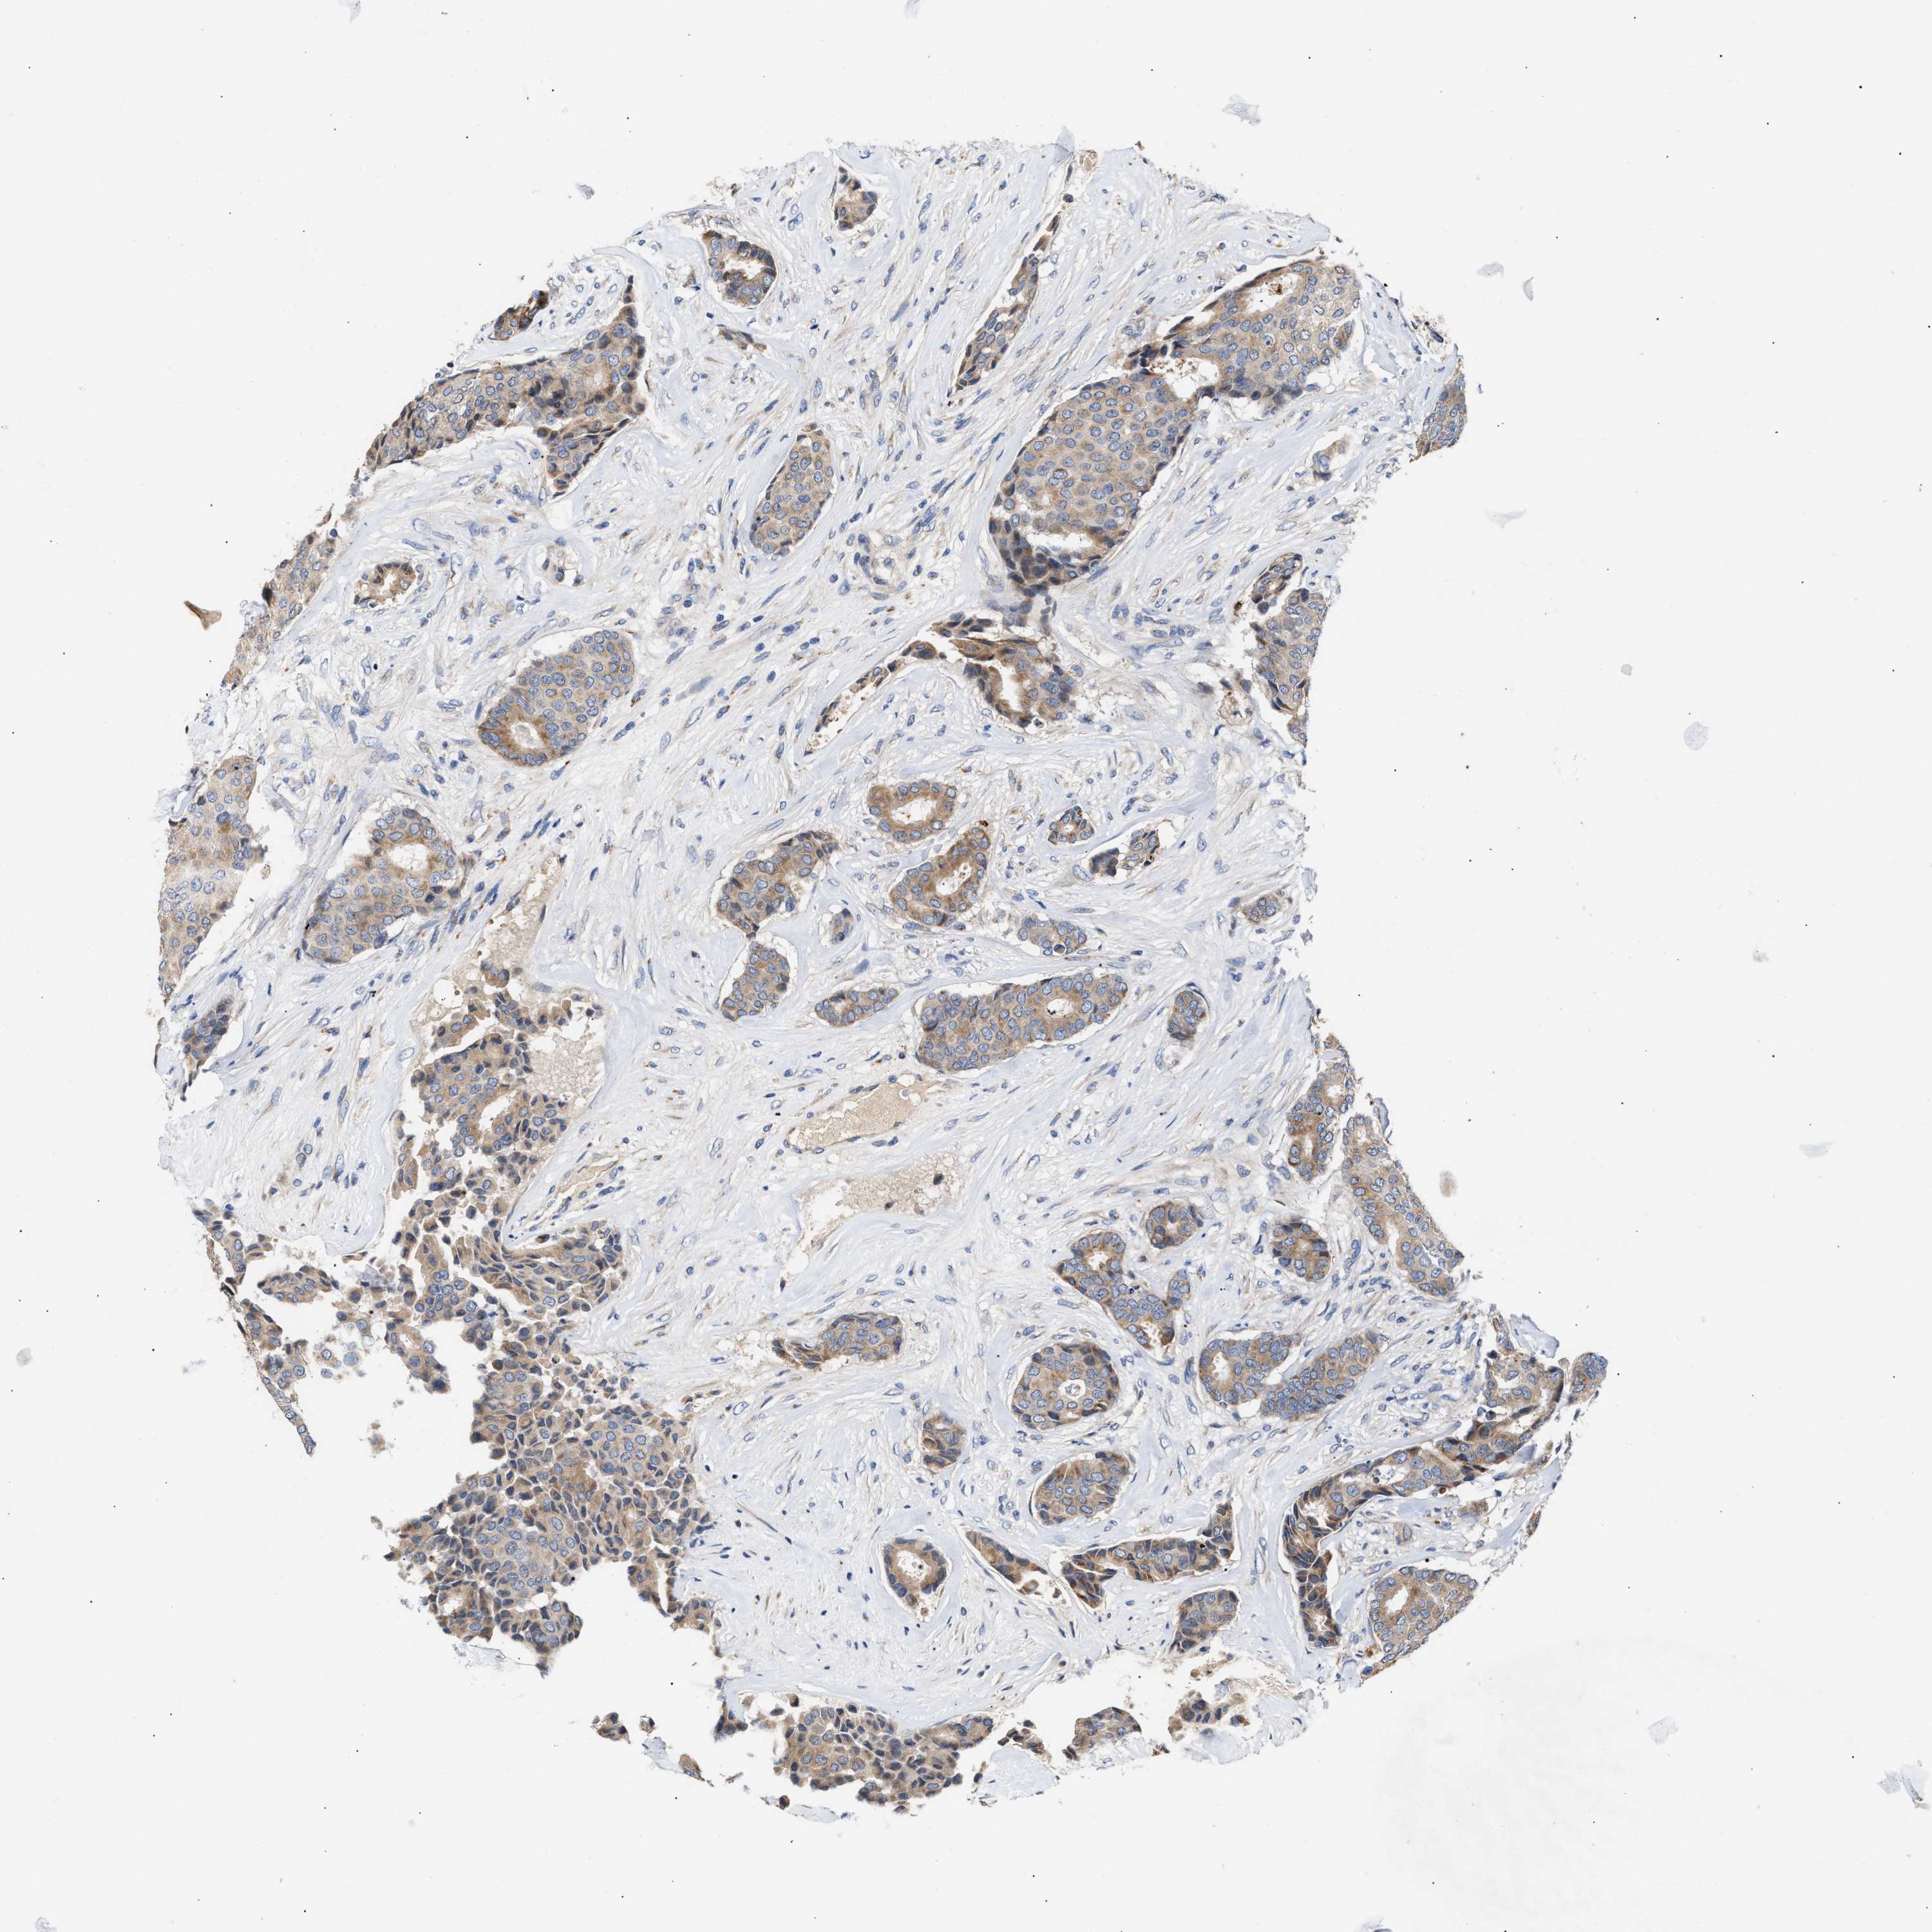

BRCA TCGA BRCA VALIDATION PROTEIN EXPRESSION

ANTIBODIES

AND

VALIDATION